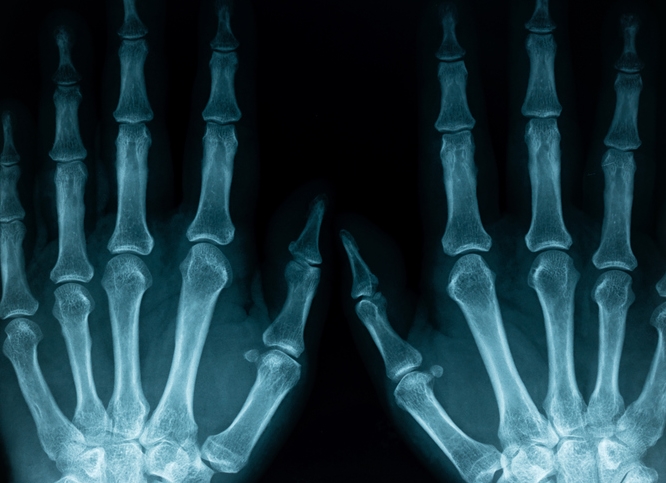

➤ 류마티스 관절염

손가락 마디나 발가락 관절이 붓고 통증이 동반된다면 손발이 붓는 이유 관절염일 가능성이 있습니다. 아침에 손이 뻣뻣하고 열감이 느껴진다면 반드시 병원 진료가 필요합니다.

마디 통증이 함께 나타난다면 관절 주위의 염증 반응을 고려해야 합니다. 류마티스 관절염, 통풍 초기 증상, 혹은 반복된 손 사용으로 인한 미세 염증일 수도 있습니다.